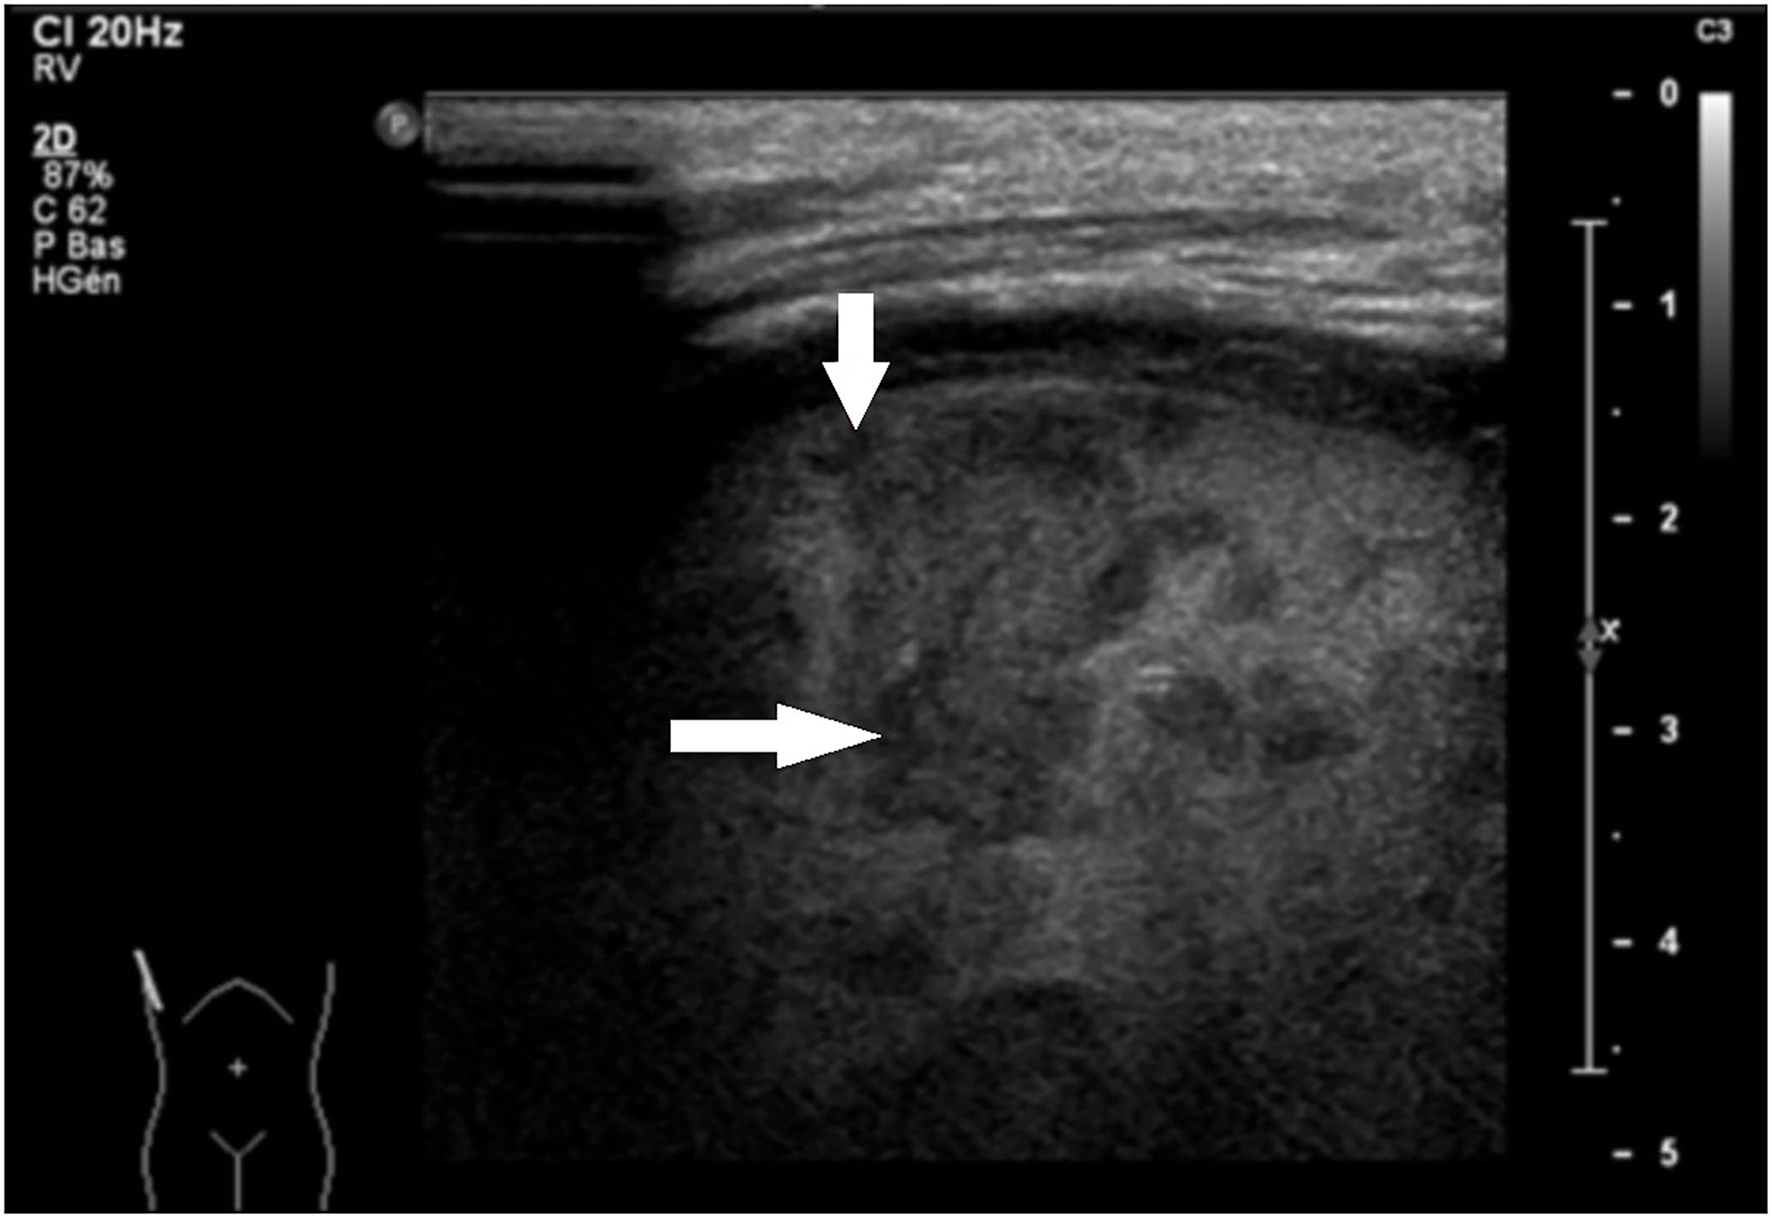

2. Lung parenchyma: consolidation with necrotic areas and developing cavities in the lung was present in 46 cases (95.8%) (Figure 2), and atelectasis (in adjacent lobes) was depicted in 33 cases (68.8%).

Figure 2

Sagittal LUS view of the right lung in an 8-year-old patient with fever and dyspnea. Heterogeneity of the right lung parenchyma corresponding to necrosis areas is clearly visible.